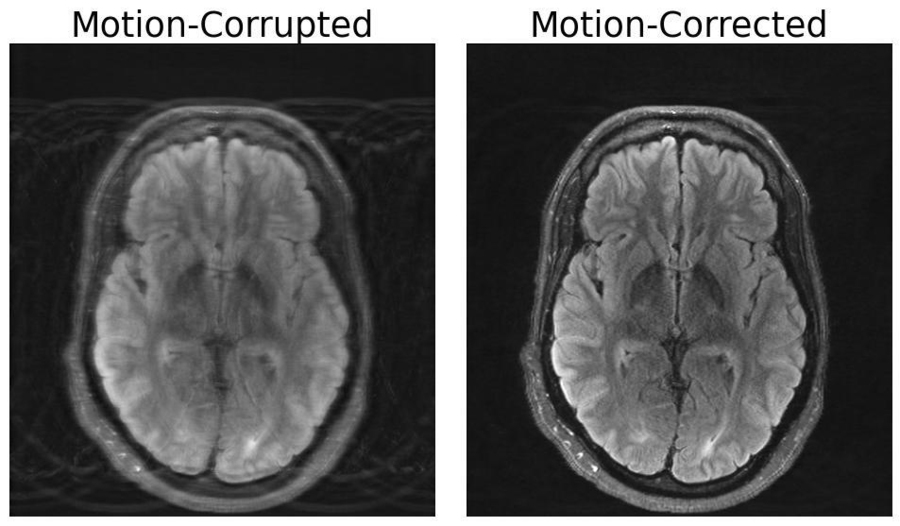

- Motion Artifacts (MRI/CT): Patient movement during a scan is a common problem, causing blurring, ghosting, and streaking that can render an image undiagnostic . Retrospective correction techniques use algorithms to estimate the motion that occurred and computationally reverse its effects. Traditional methods like PROPELLER for MRI have been effective, but modern deep learning models are showing remarkable success. These models can be trained to recognize the specific patterns of motion artifacts and generate a motion-free image, combining physics-based models with deep learning to avoid creating unrealistic "hallucinations" .

- Motion Artifacts: As previously discussed, this is the most prevalent artifact in MRI due to longer scan times. It manifests as ghosting, blurring, and smearing.